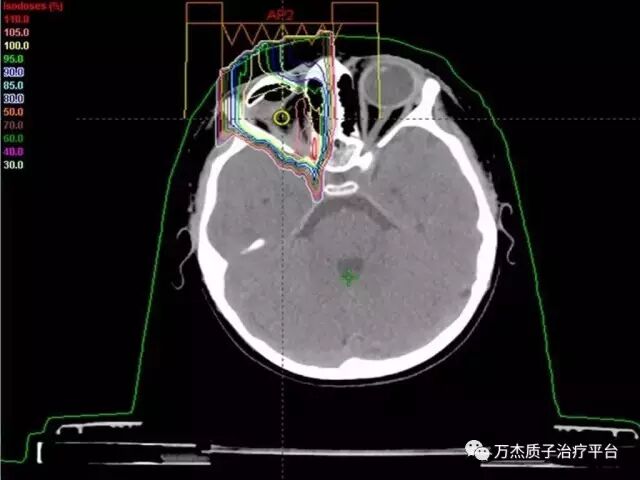

质子治疗剂量分布:对侧眼睛、视神经及脑组织均受到良好保护;

俄罗斯3岁小患者五年随访复查,未见复发迹象。